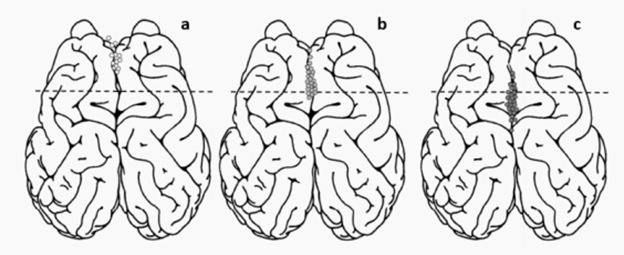

为了减轻与帕金森震颤和癫痫发作相关的症状,进入丘脑枕叶和前核是必要的。Opie等人使用商用的支架来安装铂电极,每个电极都焊接到一根绝缘的铂钨丝上。每个支架在不同的方向上放置6-12个电极,使用内径小于1.1 mm的导管植入血管。通过绵羊的颈静脉植入,在电极整合到血管壁后约4周内进行电刺激。在8只动物中,共放置了67个支架电极来刺激运动皮层。

来自6只动物的39个电极中,诱导了可观察到的和可重复的面部和肢体反应。剩下的28个电极没有引起任何反应(无效反应),包括两只没有观察到任何反应的动物。通过刺激运动皮层的不同区域所引起的反应类型如图6所示。诱导面部反应的电极位于中央沟静脉前平均距离12.8±1.4 mm,阈值电流范围为3-7.5 mA,平均刺激强度为5.3±0.4 mA。刺激嘴唇和面部的电流强度分别为4.5±0.9 mA和5.6±0.4 mA。结果表明,电极取向对电感应没有影响,因为有效的电极在不同方向上都有电刺激。

图6 (a)在嘴唇和面部引起反应的电刺激的位置 (b)诱导颌、颈部和前肢反应的电刺激位置(c)电刺激的位置没有观察到反应的区域产生的诱导反应